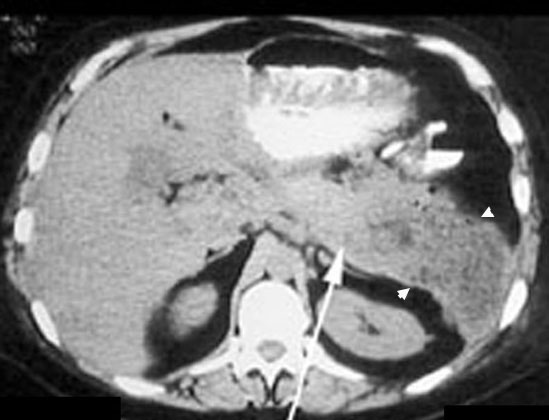

Renal abscess

CT shows a large mass in the left renal area with multiple air pockets and absence of functioning renal parenchyma.